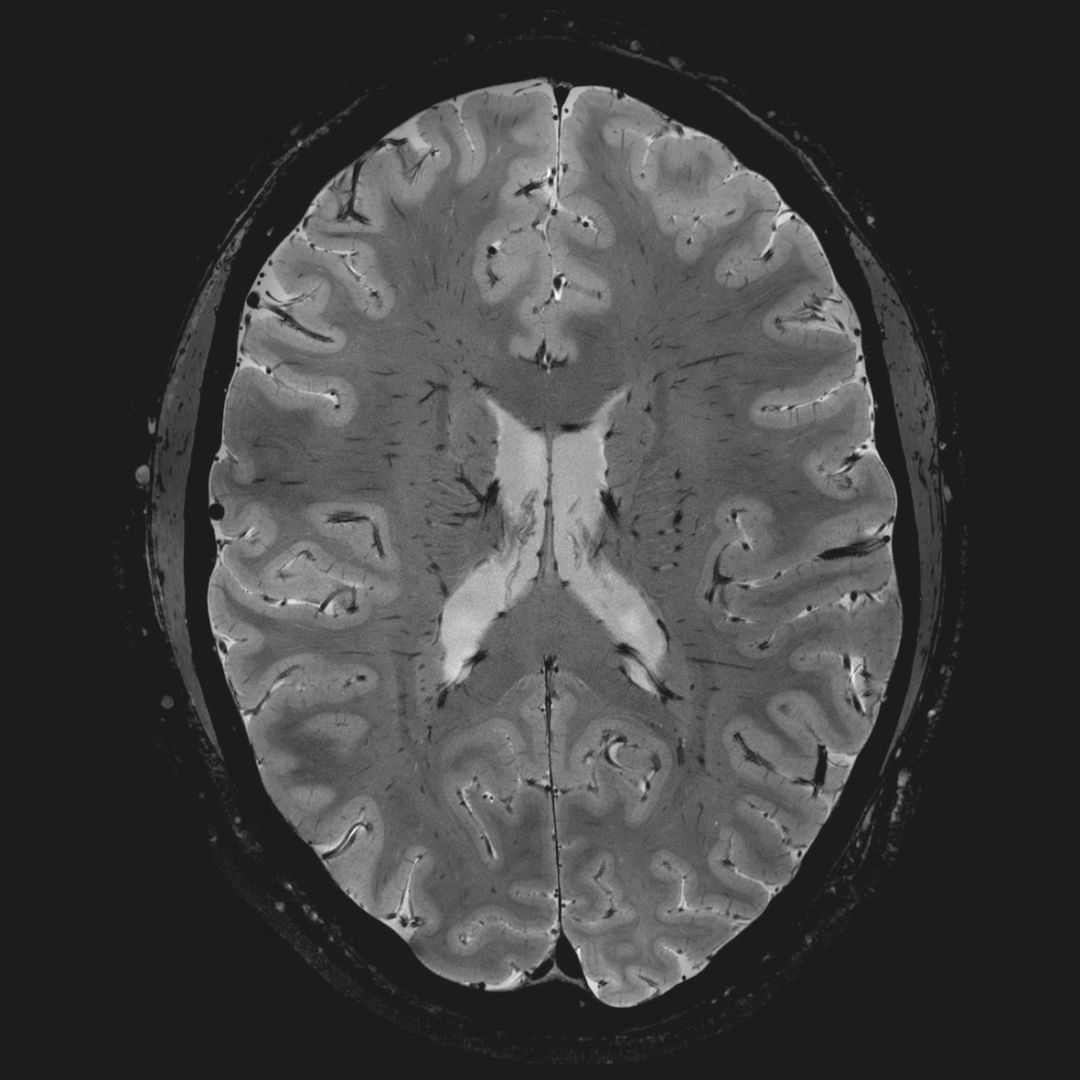

超精細(xì)的解剖細(xì)節(jié):T2對(duì)比

0.17 x 0.17 x 0.8毫米分辨率超高。